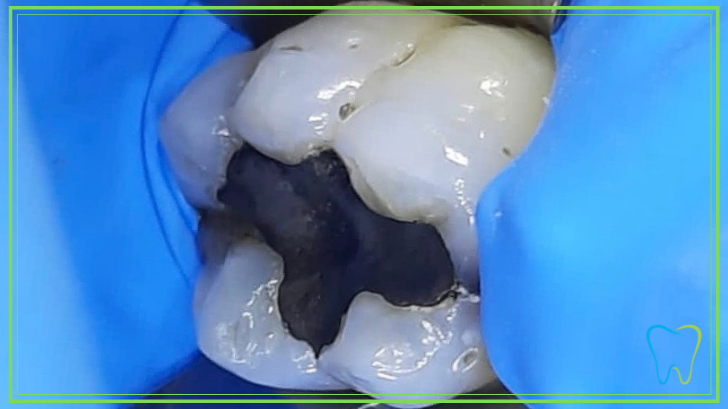

1- Isolamento del dente con la diga di gomma

La diga di gomma isola completamente il dente interessato dal resto della bocca.

In tal modo le particelle di amalgama dentale, durante la rimozione, vengono completamente catturate dal sistema di aspirazione della poltrona odontoiatrica.

La diga di gomma annulla completamente il rischio che il paziente possa ingerire particelle tossiche durante l’intervento, a tutto vantaggio di un trattamento non invasivo e rischioso per la salute.